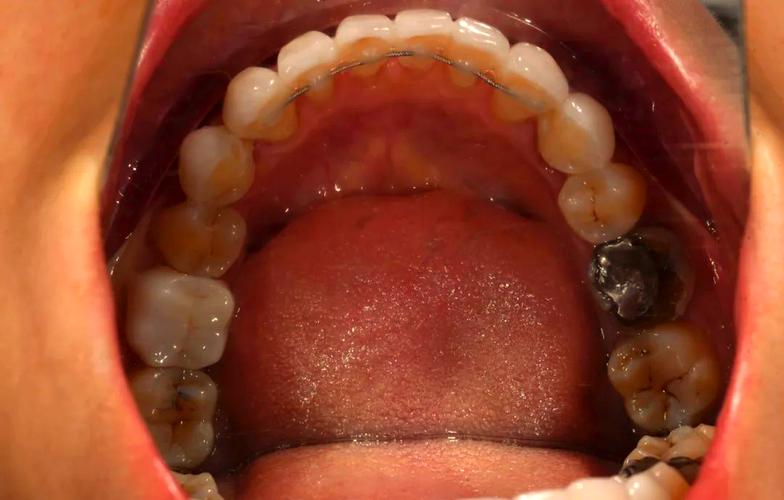

- 牙齿移位:矫正结束后,牙齿周围的牙槽骨仍处于改建稳定期,若未按医嘱佩戴保持器,牙齿可能缓慢移位,导致保持器与牙齿不匹配;

- 咬合变化:夜磨牙、紧咬牙等不良习惯,会通过保持器对牙齿产生异常力量,长期作用下导致保持器变形。

牙齿反弹移位

这是最直接也是最严重的后果,保持器的作用是“记忆”矫正后的牙齿位置,变形后无法提供持续、稳定的保持力,牙齿会在肌肉力量(如舌肌、唇肌)和咬合力的作用下逐渐移位,常见表现为:前牙拥挤、牙缝变大、牙齿扭转等,严重时甚至需要二次矫正。

变形的保持器与牙齿之间会产生缝隙,容易藏匿食物残渣;若清洁不到位,会形成牙菌斑堆积,增加龋齿、牙周炎的风险,部分材质变形后表面粗糙,更易附着细菌,进一步加剧口腔问题。